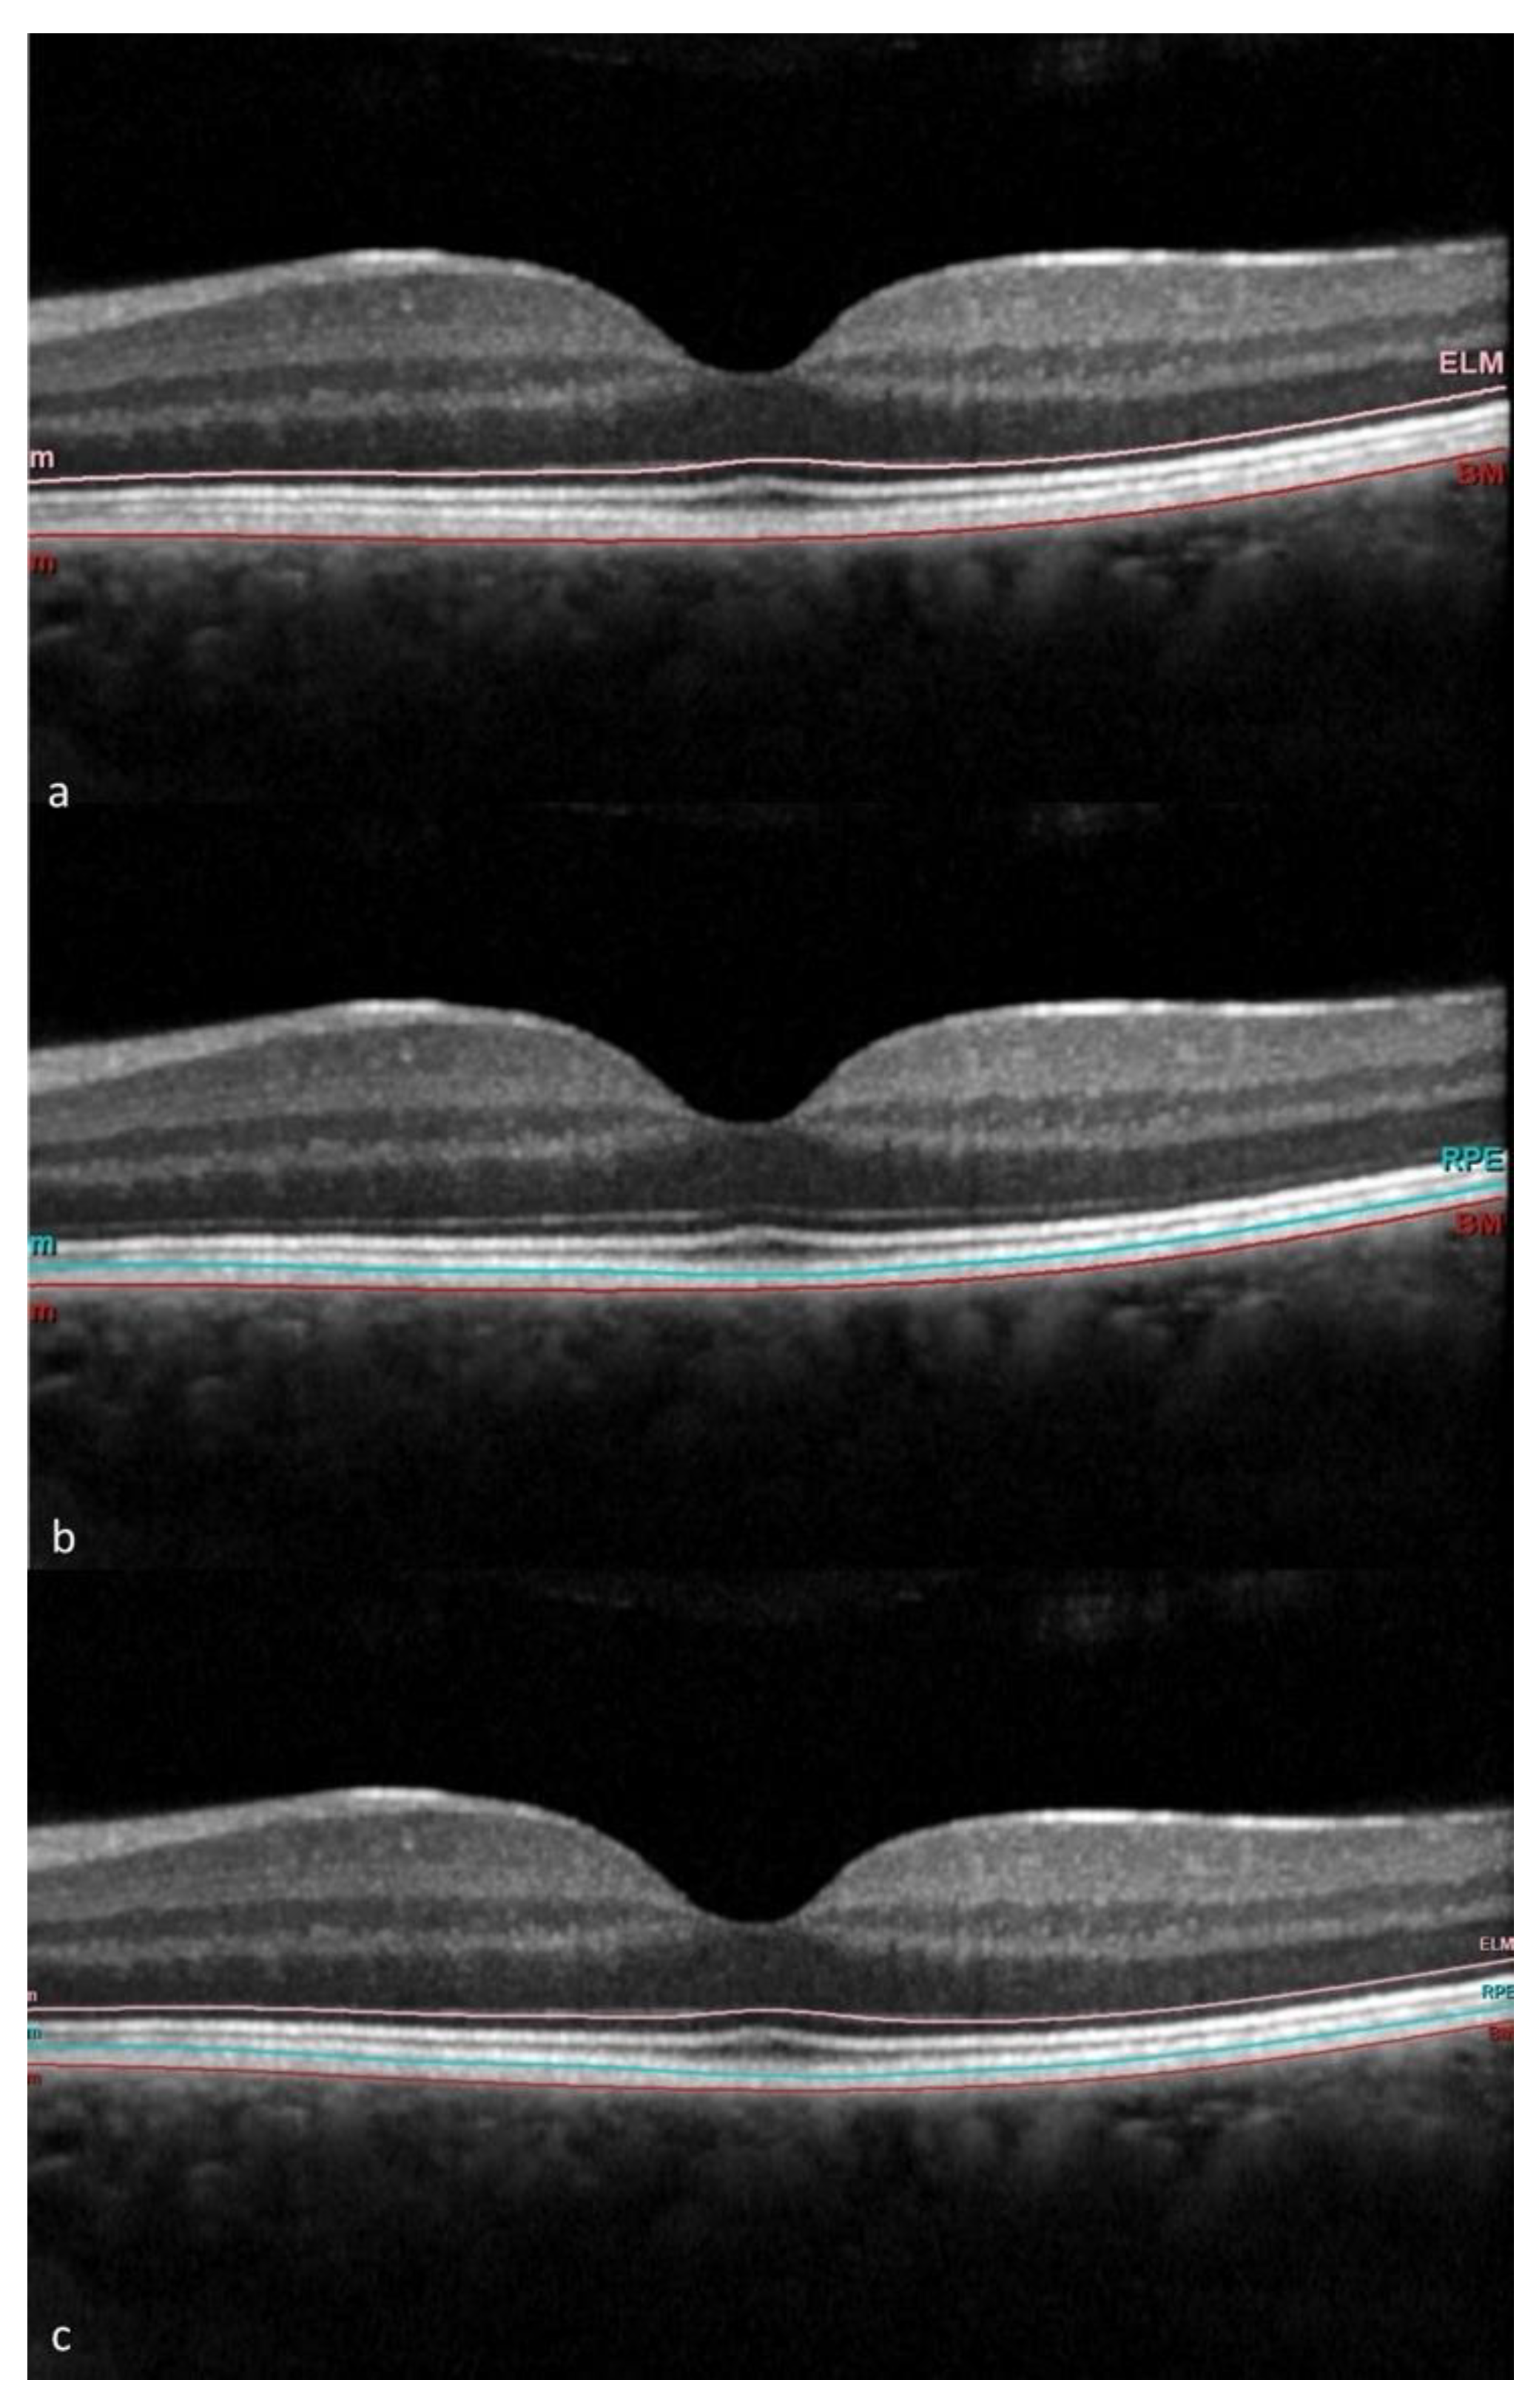

2.2. Imaging

3.2. OCT and OCTA Parameters